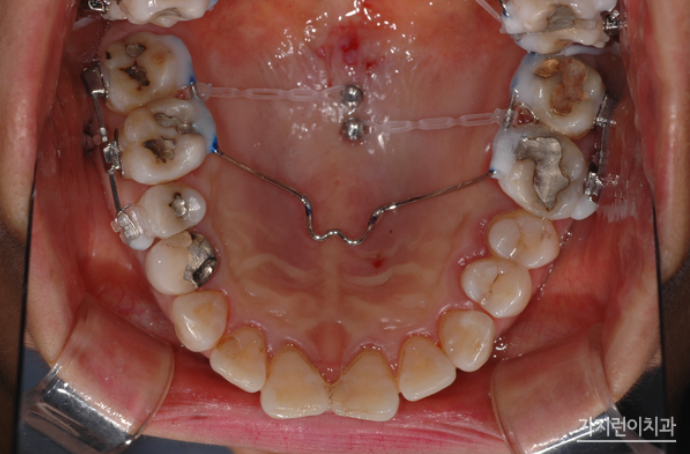

치아 상실 시 치료를 미루다가 방치하는 경우가 생각보다 많은데요. 치아 상실을 방치하면 빈 공간으로 치아가 이동하면서 치열이 무너질 수 있고, 또 잇몸 퇴축 현상이 일어나면서 추후 임플란트 시 문제가 될 수 있습니다. 그래서 환자분의 경우 치료를 통해 하악 구치부에 임플란트를 식립할 수 있었는데요. 상악 구치부의 함입을 위해 미니스크류를 식립했고 충분한 힘이 전해질 수 있도록 설계했습니다. 원래대로라면 하악 좌우 대구치 2개 및 제2소구치까지 모두 여섯 개의 임플란트가 필요했지만 이렇게 설계하면 임플란트를 4개만 심을 수 있었는데요.

구치 함입 치료를 시작하고 5개월이 되었을 때 하악구치부에 임플란트 기둥을 식립했는데요. 함입 치료 7개월 차에 임시크라운을 올렸습니다. 이 과정 역시 어려운 난이도인데요. 상하악 전치의 뻐드러짐이 개선되면서 후방으로 이동하는 양을 정확히 계산해야 하기 때문입니다.